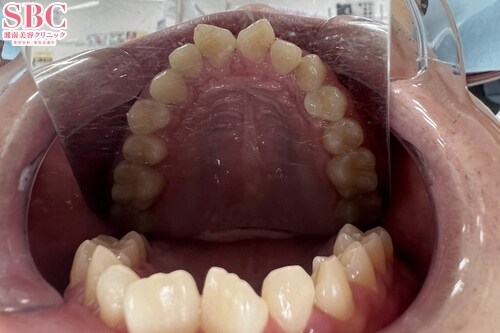

No.341927【美容歯科】歯のガタツキと捻じれを改善!

施術前

アーチから外れている部分があり、ねじれもみられます。

施術後10ヶ月後

アーチ上にきれいに歯が並び、美しい歯列となりました。

インビザラインモデレートの症例です。

追加のマウスピースもなく、26枚のマウスピースにてここまで改善されました。

マウスピース矯正は医師の設計とお客様が装着時間をお守りいただくことで

良い結果が得られます。